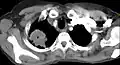

Der Pancoast-Tumor (synonym apikaler Sulkustumor) – benannt nach dem Erstbeschreiber, dem US-amerikanischen Radiologen Henry Pancoast – ist ein rasch fortschreitendes peripheres Bronchialkarzinom im Bereich der Lungenspitze (Apex pulmonis) beziehungsweise der oberen Lungenfurche, welches relativ rasch auf Rippen, Halsweichteile, Armgeflecht und Wirbel übergreift. Daher wird dieser Tumor auch als „Ausbrecherkrebs“ bezeichnet.